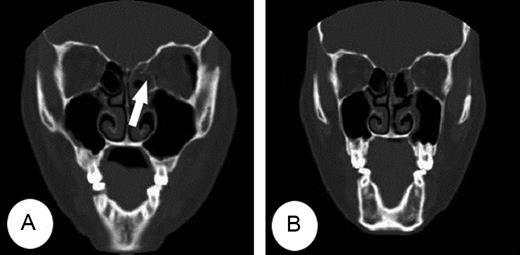

A 38-year-old woman presented diplopia with left lateral gaze after sustaining trauma to the left orbit. There was mild periorbital edema and ecchymosis at presentation. Ophthalmologic examination results were within normal except of ocular motility revealed an abduction deficit in the left eye (Fig. 1A). Computed tomography (CT) demonstrated a trapdoor-type left medial orbital wall fracture with entrapment of the medial rectus muscle (Fig. 2A). She was immediately taken to the operating room and underwent surgery under general anesthesia. Endoscopic endonasal reduction surgery for medial blowout fracture, first introduced by Yamaguchi [3] was used to expose the fractured medial orbital wall. The entrapped medial rectus muscle and herniated orbital tissue were gently released from the fracture after ethmoidectomy. The herniated orbital tissue and fractured bone were reduced to the original position, and then supported with a suitably sized Silastic sheet placed in the ethmoid sinus in an inverse U shape. A piece of Merocel® was packed between the Silastic sheets to provide support and prevent orbital tissue herniation, which were removed 4 weeks later at out-patients clinic (Fig. 3). The patient's ocular symptoms completely resolved 3 days postoperatively (Fig. 1B). Computed tomography scans demonstrated that the medial rectus muscle was reduced after surgery (Fig. 2B).

(A) CT showed a trapdoor fracture of the left medial orbital wall with the medial rectus muscle entrapped (arrow) within the fracture. (B) The entrapped medial rectus muscle and fractured medial wall were resolved on post-operative CT.